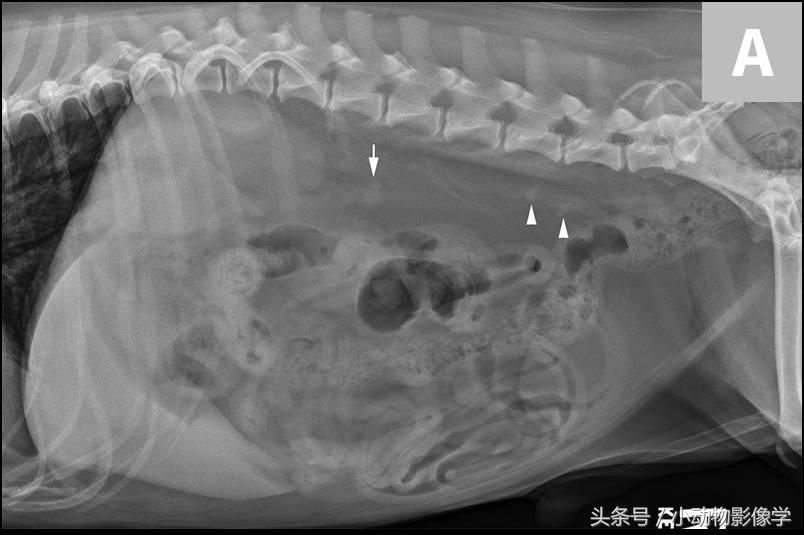

图5A、犬腹部侧位平片,可见腹膜后隙后方和肾脏背侧有两个界限清楚的椭圆形矿物化不透明重叠影像(箭头)。结合腹背位正片(这里没有显示),这些结石可能与右输尿管相关。

图5B、图5A中犬的超声图像,证实了矿物化结构位于右侧输尿管内。可见输尿管显著扩张(三角箭头之间),及输尿管腔内的两个结石引起的远端声影伪像(S)。